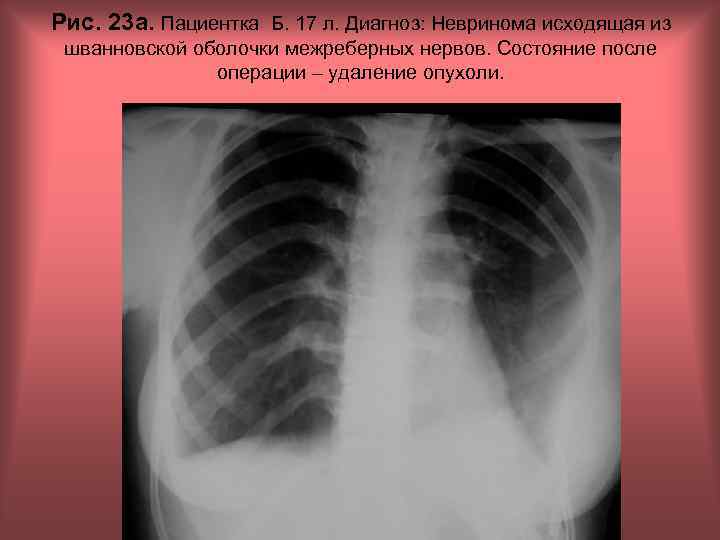

Рис. 23 а. Пациентка Б. 17 л. Диагноз: Невринома исходящая из шванновской оболочки межреберных нервов. Состояние после операции – удаление опухоли. Н. С. Воротынцева, С. С. Гольев Рентгенопульмонология